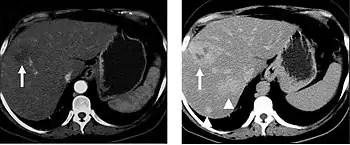

The late arterial phase is timed to correspond to the peak concentration of contrast material in highly vascular tumors and is performed approximately 20–35 seconds after the injection of intravenous contrast. Early arterial phase imaging is predominantly utilized for angiography and will be discussed separately. Late arterial phase imaging is almost always performed in conjunction with other phases (e.g. portal venous phase) to allow more complete characterization of any identified abnormalities (figure 4). The primary indication for a late arterial phase is for the evaluation of hypervascular tumors of the liver such as hepatocellular carcinoma or hypervascular metastases (figure 4). Typical hypervascular tumors for which this would be used include: hepatocellular carcinoma; renal cell carcinoma; melanoma; carcinoid/neuroendocrine tumors; some sarcomas; choriocarcinoma; and thyroid carcinoma. Although a “hypervascular”, biphasic evaluation would generally be used for these patients, note that a single phase is often adequate for follow up imaging.

When evaluating hepatic masses, it can be advantageous to have both late arterial and portal venous phase images (biphasic imaging, figure 4) since some tumors enhance briskly during the arterial phase (hepatocellular carcinoma, hepatic adenoma, follicular nodular hyperplasia (FNH), and hypervascular metastasis), but may be occult or difficult to characterize on portal venous phase imaging alone (figure 6). However, it should be stressed that the addition of late arterial phase images is only indicated if one of these tumors is suspected, or if there is a need for further characterization of a hepatic mass, since the large majority of patients will not benefit from the addition of this phase. In addition, if there is a need to definitively characterize a hepatic mass, MRI is generally more sensitive and specific, with no associated radiation dose.